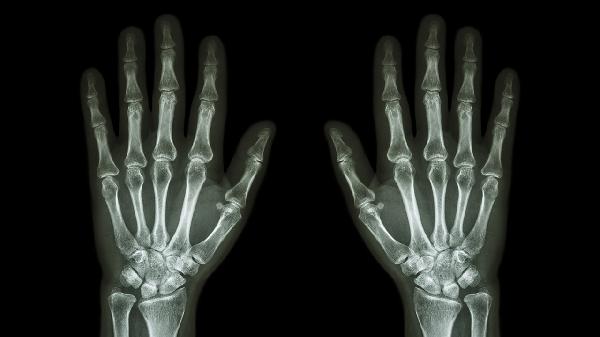

关节软骨轻微退化可能引起偶发刺痛,多发生于中老年或长期手工劳动者。X线检查可见关节间隙狭窄。可补充硫酸氨基葡萄糖胶囊,配合关节保护性锻炼,避免提握重物加重损伤。